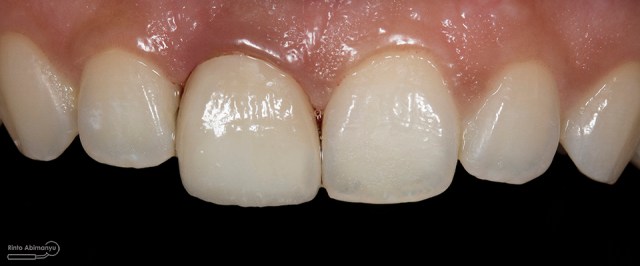

Begini hasil akhir setelah sementasi crown…

Foto klinis setelah pemasangan crown

Alhamdulillah pasien nya senang sekali…. dia puas dan saya pun senang karena dapat memenuhi keinginan pasien…..

Nah ini resume foto before dan after perawatannya…